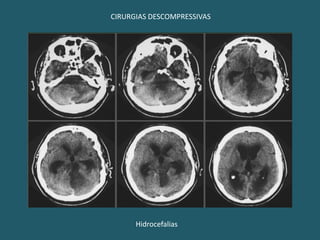

CIRURGIAS DESCOMPRESSIVASHidrocefalias